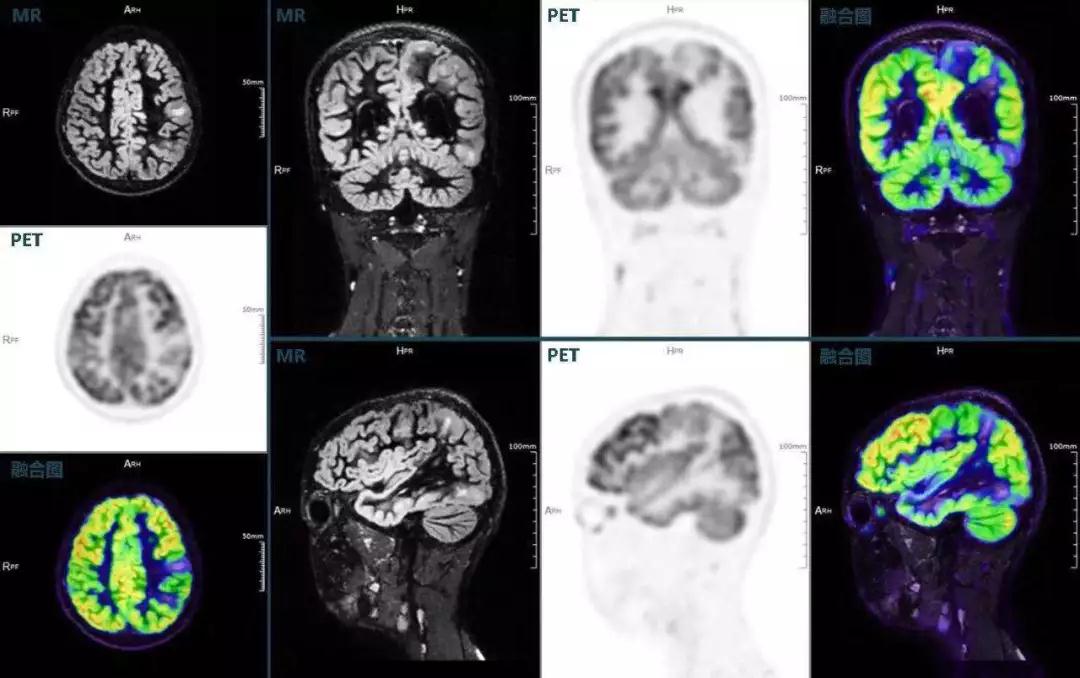

不僅如此,聯(lián)影“時(shí)空一體”超清TOF PET/MR還搭載了大量可用于神經(jīng)疾病領(lǐng)域的高級(jí)應(yīng)用,如DIR(Double Inversion Recovery雙反轉(zhuǎn)恢復(fù))序列能夠清晰顯示大腦皮層的結(jié)構(gòu)成像,對(duì)于皮層腫脹,膠質(zhì)增生等癲癇的影像征象都能清楚呈現(xiàn);DTI(Diffusion Tensor Imaging彌散張量成像)高級(jí)應(yīng)用能夠顯示細(xì)小的神經(jīng)纖維束缺損,以更加定量的形式為醫(yī)生提供一個(gè)全新的診斷維度,輔助醫(yī)生精準(zhǔn)診斷。

(結(jié)節(jié)性硬化,MR DIR序列清晰顯示腦皮層病理改變,PET顯示了病灶區(qū)域FDG的低濃聚。PET/MR融合顯像同時(shí)提供了結(jié)構(gòu)異常改變和功能變化的信息。)